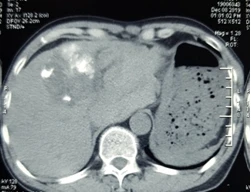

Cụ ông vỡ u gan, máu tràn ngập ổ bụng mà không hề biết

Các bác sĩ Bệnh viện Ung Bướu Hà Nội vừa thực hiện thành công ca cấp cứu u gan vỡ gây mất máu cấp, có nguy cơ tử vong cao nếu không được can thiệp kịp thời. Bệnh nhân được cầm máu bằng phương pháp nút tắc động mạch gan, giúp vượt qua “cửa tử”.